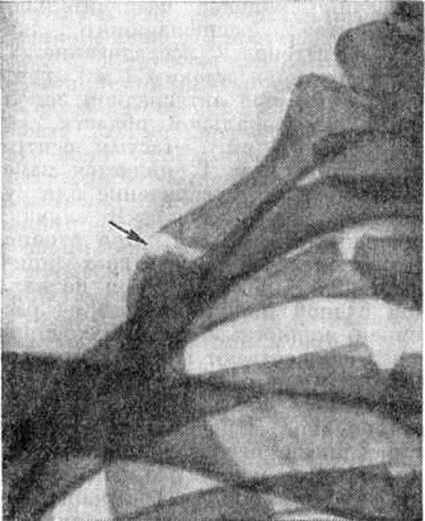

Решающее значение в дифференциальной диагностике имеют результаты рентгенологическое исследования. На рентгенограммах иногда уже при первом исследовании, а чаще при динамическом наблюдении выявляется асимметрия обызвествления и строения соответствующих участков ребер. На стороне поражения обызвествление более выражено, ребро выглядит толще, массивнее. После окостенения всего реберного хряща грудино-рёберные суставы могут стать видимыми и в них может наблюдаться картина деформирующего артроза (смотри полный свод знаний: Артрозы). При локализации поражения в области костно-хрящевых соединений (чаще в I ребре) на рентгенограмме видна типичная зона патологический функциональной перестройки — полоса просветления с булавовидным утолщением кости на этом уровне за счёт периостального костеобразования, иногда с развитием неоартроза (рисунок). Существенную помощь в диагностике может оказать томографическое исследование в прямой передней проекции (смотри полный свод знаний: Томография).

Рис

рентгенограмма части грудной клетки больного с синдромом Титце (прямая проекция): стрелкой указан неоартроз, развившийся в зоне патологической перестройки ткани I ребра.